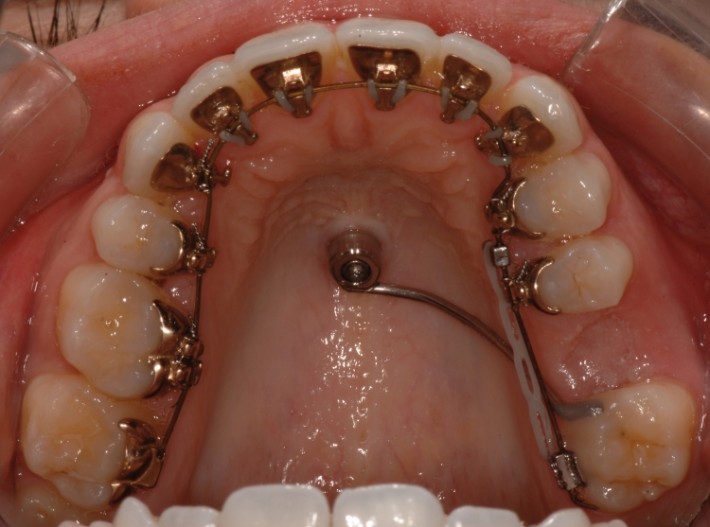

Gaumenimplantat

Im vorliegenden Fall hilft ein Gaumenimplantat mit einer entsprechenden Apparatur die Mahlzähne nach hinten (distal) zu bewegen, um eine korrekte Verzahnung einzustellen oder einen Engstand ohne Extraktion und ohne abnehmbare Geräte (z.B. Headgear) aufzulösen.

Auch die Gaumenapparatur „Top Jet“ mit zwei Minischrauben im Gaumen ermöglicht eine Distalisierung der Mahlzähne, ohne dass eine Mitarbeit der Patient:innen notwendig wäre (ersetzt den Headgear). Indem der Top Jet innen befestigt wird und die Brackets auf den Frontzähnen am Beginn der Behandlung noch nicht notwendig sind, erfolgt der erste Teil der Behandlung unsichtbar und damit ohne ästhetische Beeinträchtigung.